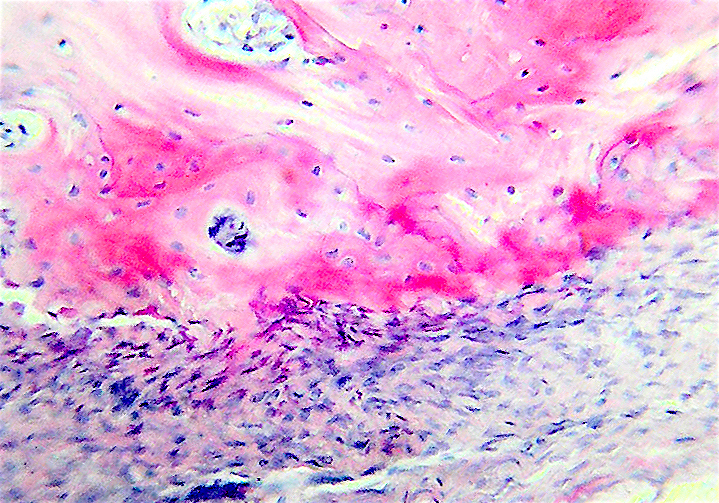

Пузырьки образуются из митохондриий и выбрасываются клетками, они обызвествляют кости, в них образуются игольчатые отложения.

Они ферментативно активны.

Первым это открыл Андерсон в хрящевой ткани в 1976, наблюдая процесс обызвествления хряща.